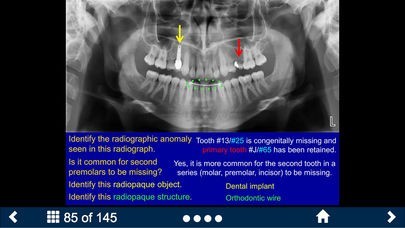

Oral Radiology - SecondLookのスクリーンショット

The SecondLook™ Oral Radiology application will help learners of the dental sciences to self-test their level of knowledge and ability to recognize technical errors, anatomical structures, dental disease, and maxillofacial pathology in intraoral and panoramic radiographs as well as CBCT scans. This app covers the following topics: Radiographic Anatomy (on Periapical & Bitewing Radiographs); Radiographic Anatomy (on Panoramic Radiographs); Image Quality and Common Errors; Radiographic Interpretation; Radiographic Anomalies; Buccal Object Rule (BOR); Cone Beam Computed Tomography (CBCT); Pediatric Radiology; and Presentations of Oral Pathologies (including inflammatory lesions, cyst and cyst- like lesions, benign tumors of the jaws, malignant diseases, bone and systemic diseases).